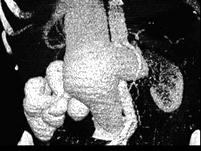

男,18岁,请根据所示图像,选择最可能诊断 ( )A、右侧肾癌B、右肾动静脉畸形C、右肾出血D、右肾囊肿E、右肾积水

问题 男,18岁,请根据所示图像,选择最可能诊断 ( )

选项 A、右侧肾癌 B、右肾动静脉畸形 C、右肾出血 D、右肾囊肿 E、右肾积水

答案 B